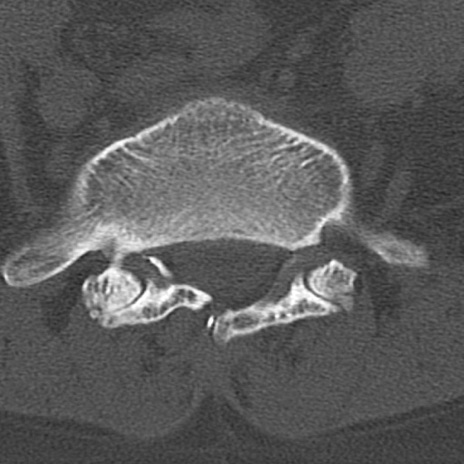

【整形】TIPS症例4 腰椎CT(横断像)

腰椎CT

横断像と矢状断像